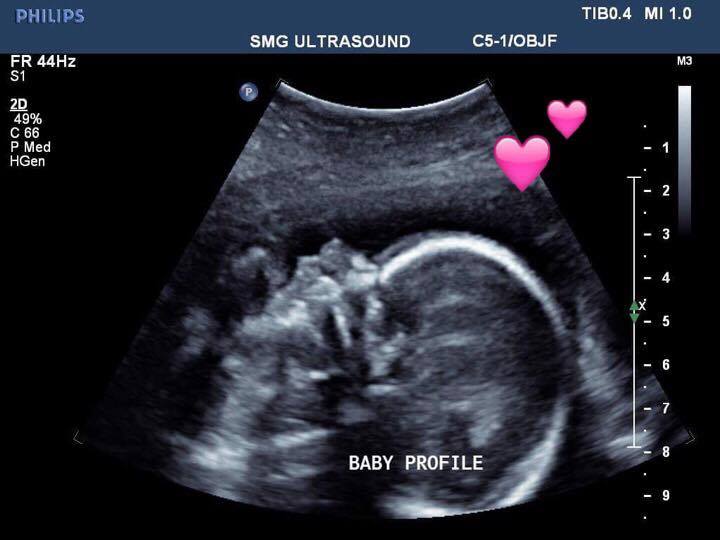

The Zimmer baby at 21 weeks in utero. Supplied